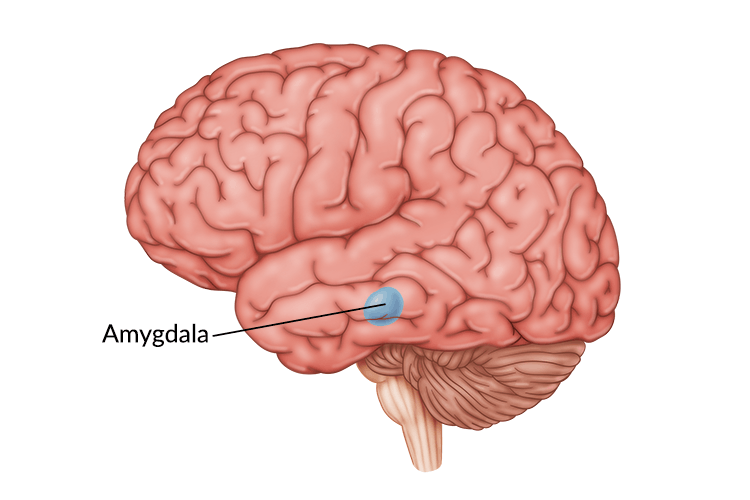

Amygdala: What It Is and What It Controls

Know Your Brain: Amygdala

Amygdala Function and Location

Amygdala's Location and Function

Amygdala: Anatomy, Location, and Function

Where in the brain is the amygdala located? - Quora